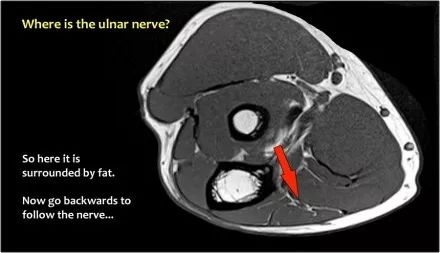

尺神经:在这里,我们看到了肘管内的尺神经。尺骨侧支带的后带形成隧道的底部,而支持带形成屋顶。

因此,当我们回到图像时,您会发现很难找到神经。任何这些皮下结构都可以是转位神经。一种方法是远端跟随结构,直到你发现远端的尺神经位于由脂肪包围的前臂近端的正常位置。然后当你向近端跟随它时,你会发现这是皮下移位。